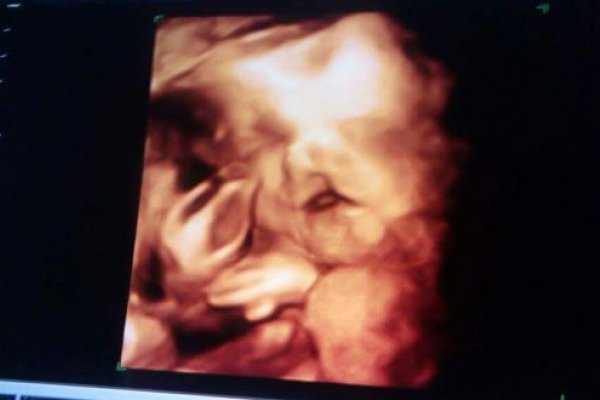

وقال الدكتور عمرو عباسي، استشاري النساء والتوليد والعقم بالمركز القومي للبحوث، والطبيب المتابع للحالة، إنه لاحظ من سونار ثلاثي ورباعي الأبعاد خلال زيارة المتابعة للأم، أن الجنين ليس له عينان نهائيًا ولا وجود لعدسة العين وأن الجلد يغطي هذا المكان، بالإضافة لعدد من العيوب الخلقية التي تضمنت إصابته بالشفة الأرنبية وقصور الأطراف باليدين والرجلين وعيوب خلقية في القلب والعمود الفقري والضلوع أيضًا، وذلك بخلاف إصابته بضمور المخ، وهو الأمر الذي جعل الطبيب المتابع للحالة يسرع في توليد الأم بعد 18 أسبوعًا فقط، ولكن الطفل مات فور ولادته بسبب إصابته أيضًا بضمور في المخ.